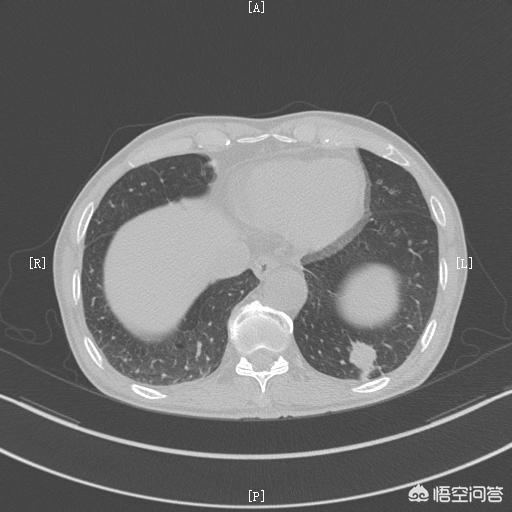

Cancer du poumon.

Pourquoi le cancer du poumon provoque-t-il une oppression thoracique et un essoufflement ? En effet, lorsque la lésion cancéreuse du poumon est relativement importante, elle entraîne une obstruction partielle des bronches, ce qui affecte la fonction pulmonaire et se traduit par l'apparition des symptômes suivantsOppression thoracique, essoufflementsymptômes du cancer du poumon. Mais en général, si le cancer du poumon se manifeste par une oppression thoracique et un essoufflement, cela signifie que le cancer du poumon est en cours de guérison.Il s'agit d'un cancer du poumon avancé.car, en général, lesLes premiers symptômes du cancer du poumon ne sont pas évidents。

En cas de cancer du poumon à un stade moyen ou avancé, outre l'oppression thoracique et l'essoufflement, il peut y avoir des signes d'oppression thoracique.Douleur sourde, douleur vague, etc.dans le cas d'un cancer central du poumon, il peut également y avoir des symptômes de cancer du poumon.le sang qui circule dans le corps (souvent comme métaphore d'une émotion forte ou d'un sang chaud)Symptômes tels que

Pour le diagnostic du cancer du poumon, la méthode de diagnostic la plus importante est l'imagerie. La radiographie du thorax permet de détecter le cancer du poumon avec des lésions plus importantes, mais pour les cancers du poumon plus petits, il est toujours nécessaire de passer l'examen médical.Tomodensitométrie du thoraxpour poser un diagnostic. Un scanner du thorax est également le meilleur moyen de dépister et de diagnostiquer le cancer du poumon. En outre, il est souvent possible deBronchoscopie à fibres optiques ou ponction guidée par CTDes examens tels que le prélèvement de tissu de la lésion et la réalisation d'une biopsie pathologique permettent d'établir le diagnostic de référence.

Une fois le cancer du poumon diagnostiqué, pour ceux qui peuvent être traités chirurgicalement, il est important deAblation chirurgicale agressiveparce que c'est le seul moyen de guérir le cancer du poumon, et pour ceux qui ne peuvent pas être traités par résection chirurgicale, il y a une option deChimiothérapie, immunothérapie, thérapie ciblée, etc.D'autres traitements pour améliorer la qualité et prolonger la survie.